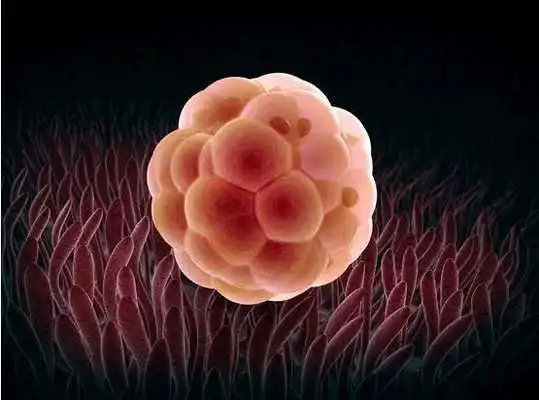

Tips ibu hamil app merupakan Informasi mengenai perkembangan janin dalam kandungan yang dirangkum berdasarkan periode Kehamilan, mulai dari Kehamilan minggu ke 1 sampai minggu ke 42.Pada Aplikasi ini dibahas tuntas mengenai tata cara dan keluhan yang sering dirasakan oleh ibu hamil pada umumnya dan bagaimana proses pembentukan janin mulai dari proses pembuahan sel telur sampai terciptanya sang bayi dimuka bumi ini.

Pada Fitur ini dibahas secara detail perkembangan kehamilan berdasarkan periode minggu kehamilan